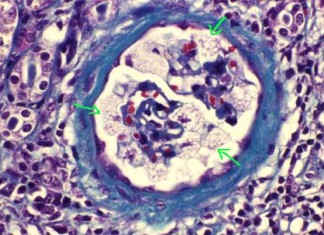

Investigadores desarrollan riñón implantable, bioingeniería (video)

Riñones de rata obtenidos desarrollados por el Hospital General de Massachusetts(MGH) fueran producidos con éxito tanto en un aparato de laboratorio y después de...